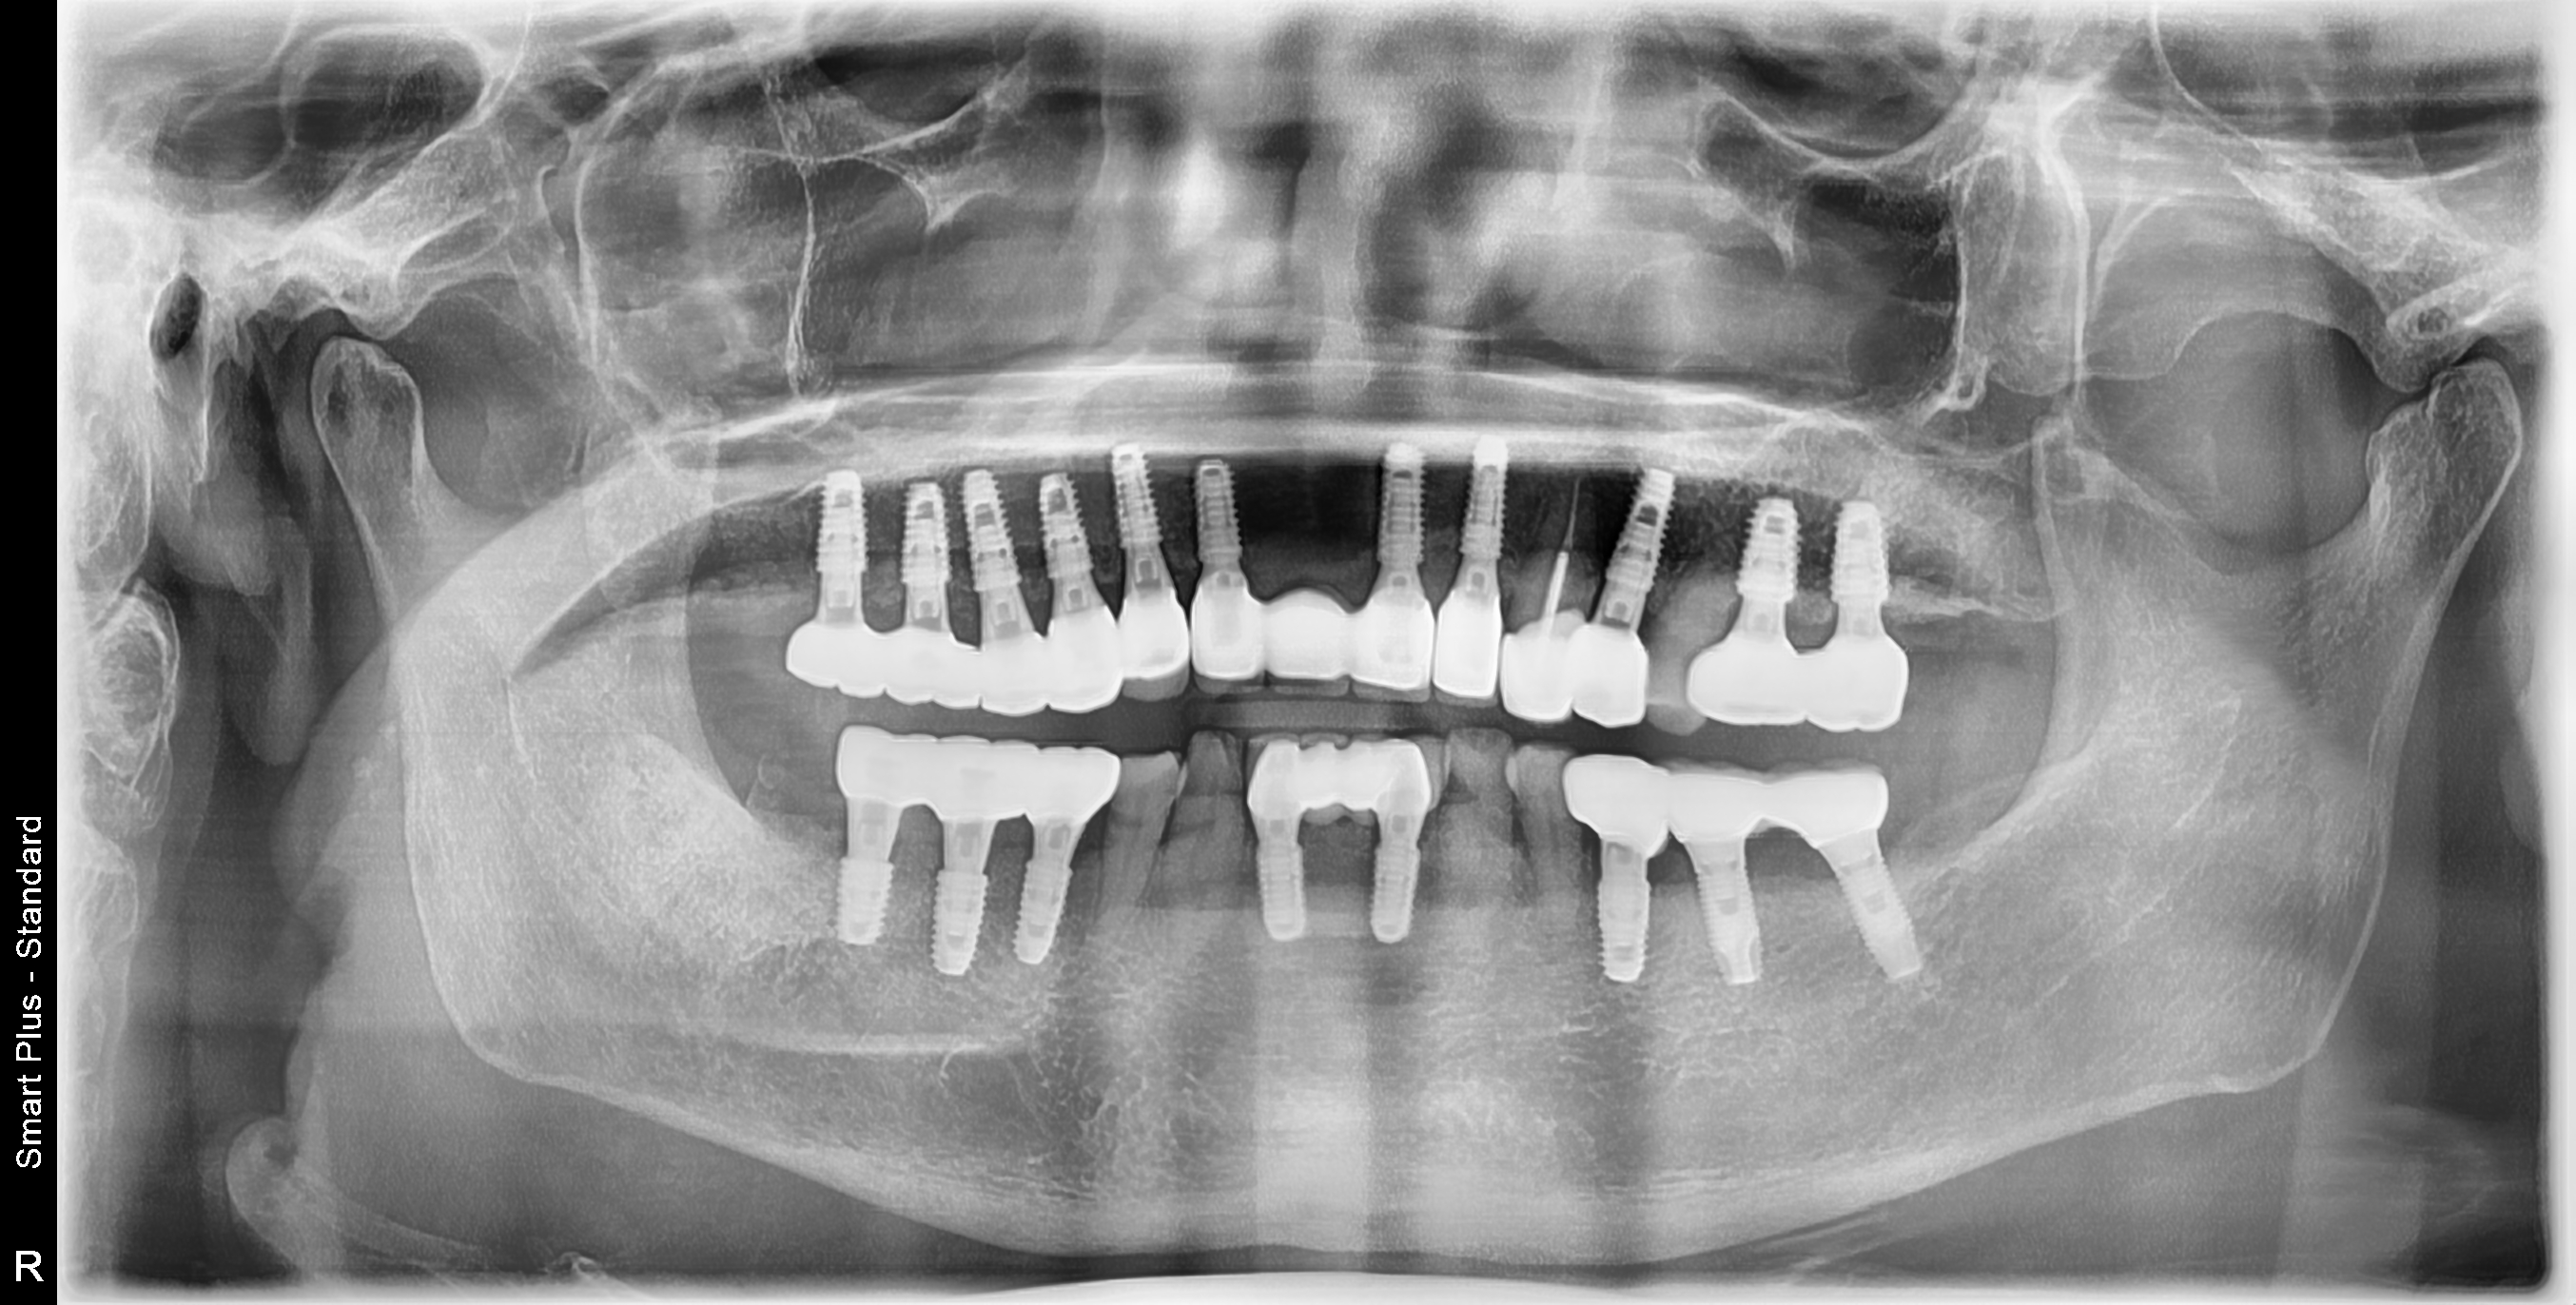

[임플란트] 제목 : 노인 임플란트

전체적으로 얇은 뼈를 가진 노인에서, 흔들리는 치아들을 빼고 임플란트와 보철치료를 시행하였습니다.